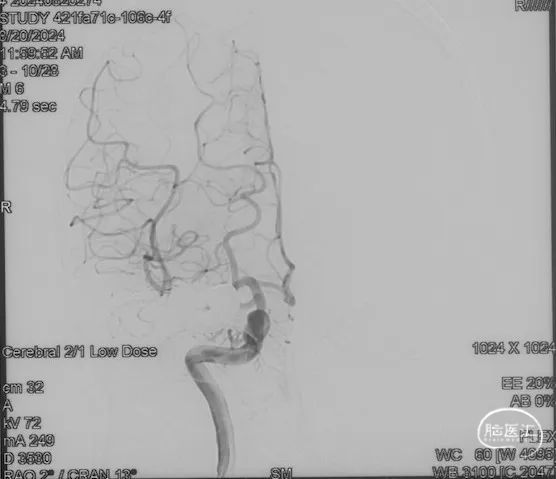

影像学的随访

术后9m

右侧颈内动脉造影未见瘘口显影及静脉早显

右侧颈外动脉造影未见瘘口显影及静脉早显

左侧椎动脉造影未见瘘口显影及静脉早显